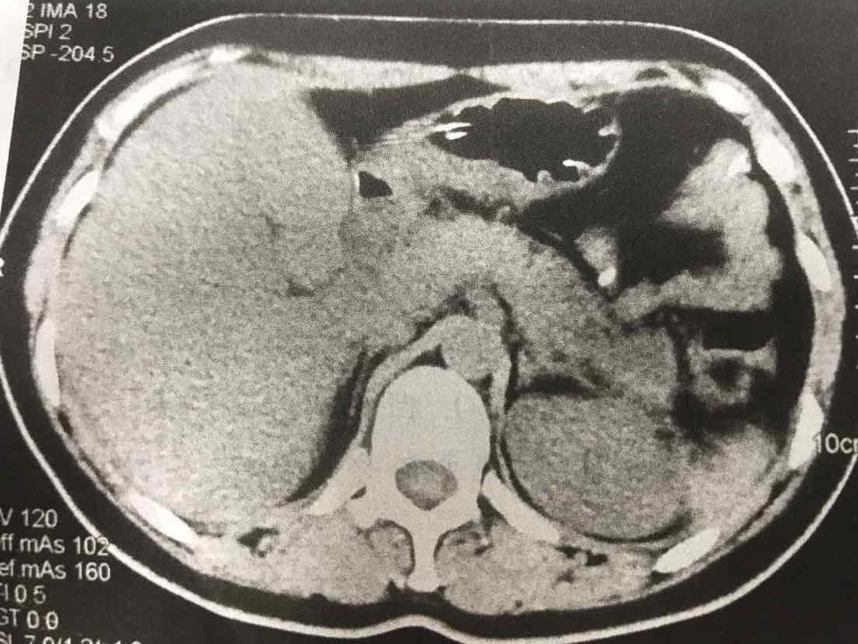

胸腹部增强CT:双侧胸腔积液,双下肺膨胀不全;胰腺周围脂肪密度不均匀增高,胰周及腹腔积液;肝内胆管轻度扩张。

患者Ranson评分>3分(血钙低,白细胞高,血糖高),BalthazarCT分级为E级,考虑为重症胰腺炎。